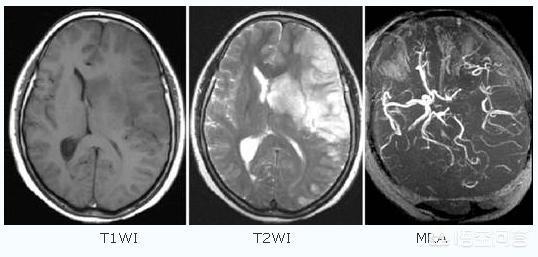

脳梗塞は、臨床的には虚血性脳卒中とも呼ばれ、アテローム性動脈硬化症、高血圧、糖尿病、冠動脈性心疾患など様々な原因によって脳の血管に血液が供給されなくなり、虚血、低酸素症、局所脳組織の壊死を引き起こす!

脳卒中は出血性脳卒中と虚血性脳卒中に分けられる。虚血性脳卒中(脳梗塞)は中国で最も多い脳卒中である。虚血性脳卒中とは、血管の閉塞により脳への血流が不足し、脳組織が虚血性壊死を起こし機能を失う病態であり、脳塞栓症や脳血栓症が代表的な原因である。虚血性脳梗塞の発症前には、突然片側の手足のしびれや脱力感、言語障害、目のかすみ、平衡感覚障害などの一時的な脳虚血症状(一般にミニ脳梗塞と呼ばれる)が出現することがあり、この症状は短期間出現し、すぐに回復します。脳卒中の重要な前兆です。..脳頸動脈の動脈硬化性プラークと狭窄は虚血性脳卒中を引き起こす重要な因子である。中高年に加え、高血圧、高コレステロール、糖尿病、長期喫煙者が最も多い。